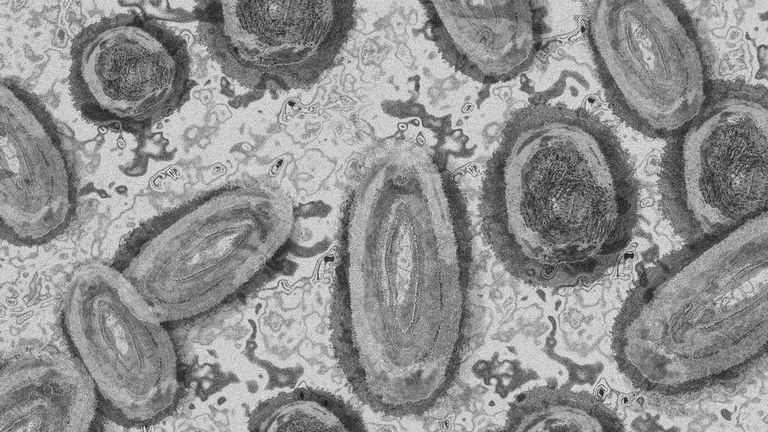

خلال دقيقتين.. جهاز استشعار بصري يكتشف فيروس جدري القرود

أعلنت دراسة جديدة عن تطوير جهاز استشعار بصري يمكنه تشخيص مرض جدري القرود بسرعة وبتكلفة منخفضة.

ومرض جدري القرود، من الأمراض الفيروسية التي تسببها سلالة من فيروسات الجدري، قد انتشر إلى أكثر من 100 دولة منذ عام 2022، مما أثار القلق الدولي. في أغسطس الماضي، أعلنت منظمة الصحة العالمية عن تفشي المرض بوصفه "حالة طوارئ صحية عامة تثير قلقاً دولياً"، ومع الحاجة الملحة لتطوير أدوات تشخيص أسرع وأكثر فعالية لمكافحة المرض، يأتي هذا الاكتشاف كحل مبتكر.